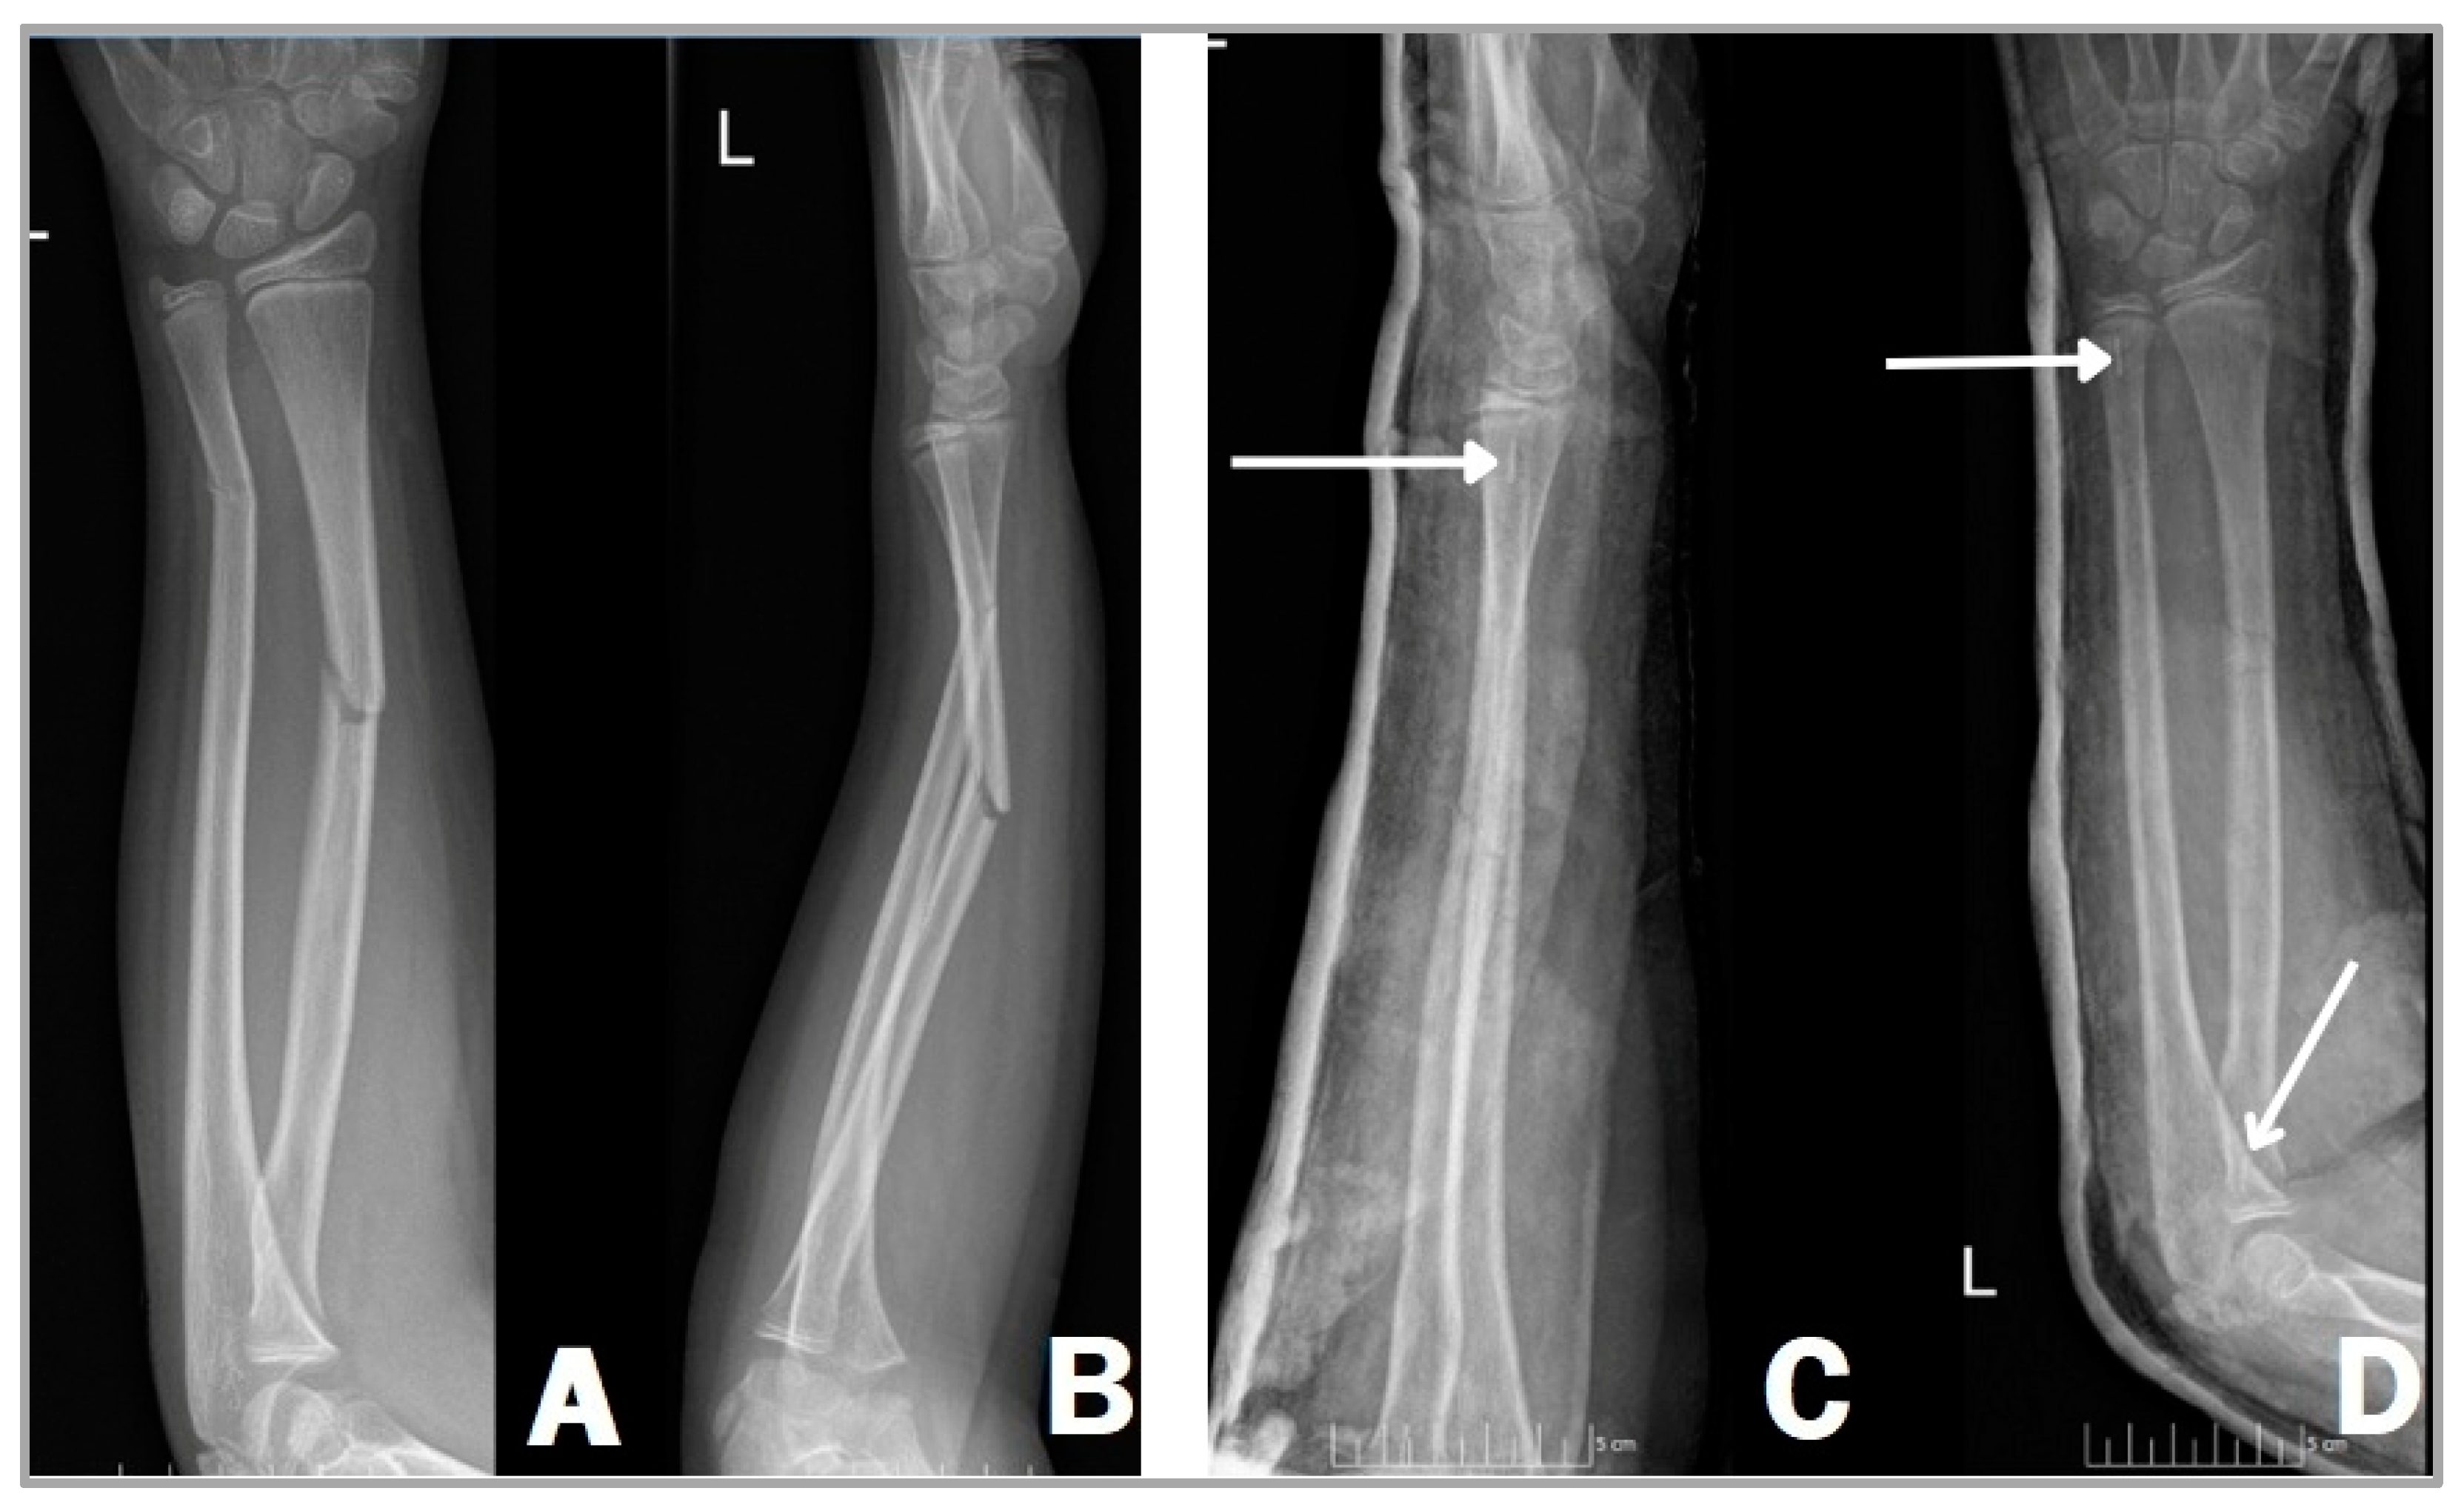

In a similar surgical technique, we can use bioabsorbable implants instead of titanium to stabilize the fracture (Figure 2). The position of the patient and the preparation are no different from the gold standard method, utilizing a supine position on a standard operating table with a radiolucent arm board [20,21]. A C-arm image intensifier is used also during this technique; however, only the radiopaque tricalcium phosphate (β-TCP) tip is visible on the film, not the entire nail as with TENs (Figure 2C,D), due to the PLGA material being radiolucent. After the reduction of the fracture, unlike the ESIN procedure, the medullary canal should be prepared with an implant-specific dilator tool when using a bioabsorbable intramedullary nail. This procedure is carried out in order to reduce the chances of implant fracture during insertion against resistance. Dilator tools are employed to create a suitable area within the canal for accommodating the implant [14,15,16]. After that, the inserted steel dilator alloys are removed and replaced by biodegradable nails (Activa IM-Nails™). This can only be achieved when both bones of the forearm are securely stabilized by the aforementioned dilators and it is also essential to remove the dilator from one bone at a time. Moreover, it is important to remove the metallic instrument from the second bone only when the resorbable implant placed in the first bone is in position and adequately stabilizes the fracture to reduce the risk of secondary displacement [22].

Figure 2.

Right forearm shaft fracture of an 11-year-old girl, showing complete fractures in both radius and ulna. Anteroposterior (A) and lateral (B) X-rays before and after surgery (C,D). Two Activa IM-Nails™ fixate the fracture in a good position. The white arrows show the radiopaque tricalcium phosphate (β-TCP) tips (C,D).